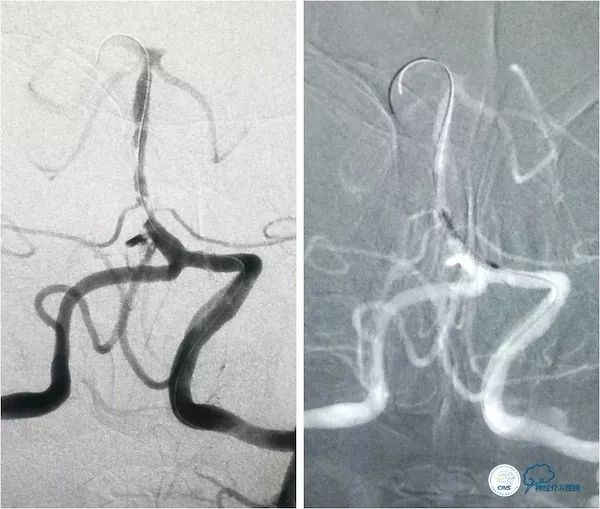

路径图下将Traxcess微导丝(0.014”,200cm)在Echelon-10辅助下放置在右大脑后动脉P2段,交换送入Transend微导丝(0.014”,300cm),沿微导丝送入Gateway(2.0mm×15mm)球囊预扩张(图15)。

图15

后更换Select Plus微导管至右侧大脑后P2段,沿微管送入Enterprise自膨式支架(4.5mm×37mm),到位后释放,造影示:支架贴壁良好,前向血流TICI3级,残余狭窄约30%(图16)。

图16